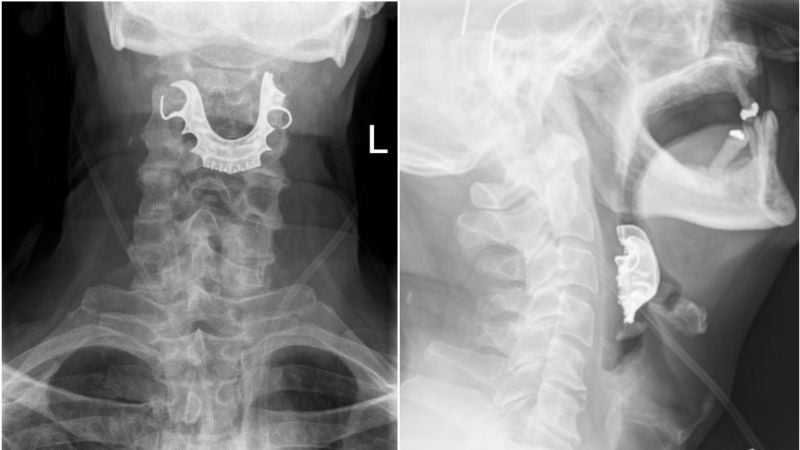

Un hombre sufre un derrame cerebral por crujirse demasiado el cuello

Un hombre de 28 años en Oklahoma se desgarró una arteria vertebral en el cuello que lo llevó a su cerebro, lo que le hizo sufrir un derrame cerebral, según informa KOCO News. Según el medio, Josh Hader, de Guthrie, Oklahoma, se rompió la arteria simplemente crujiéndose el cuello demasiado.